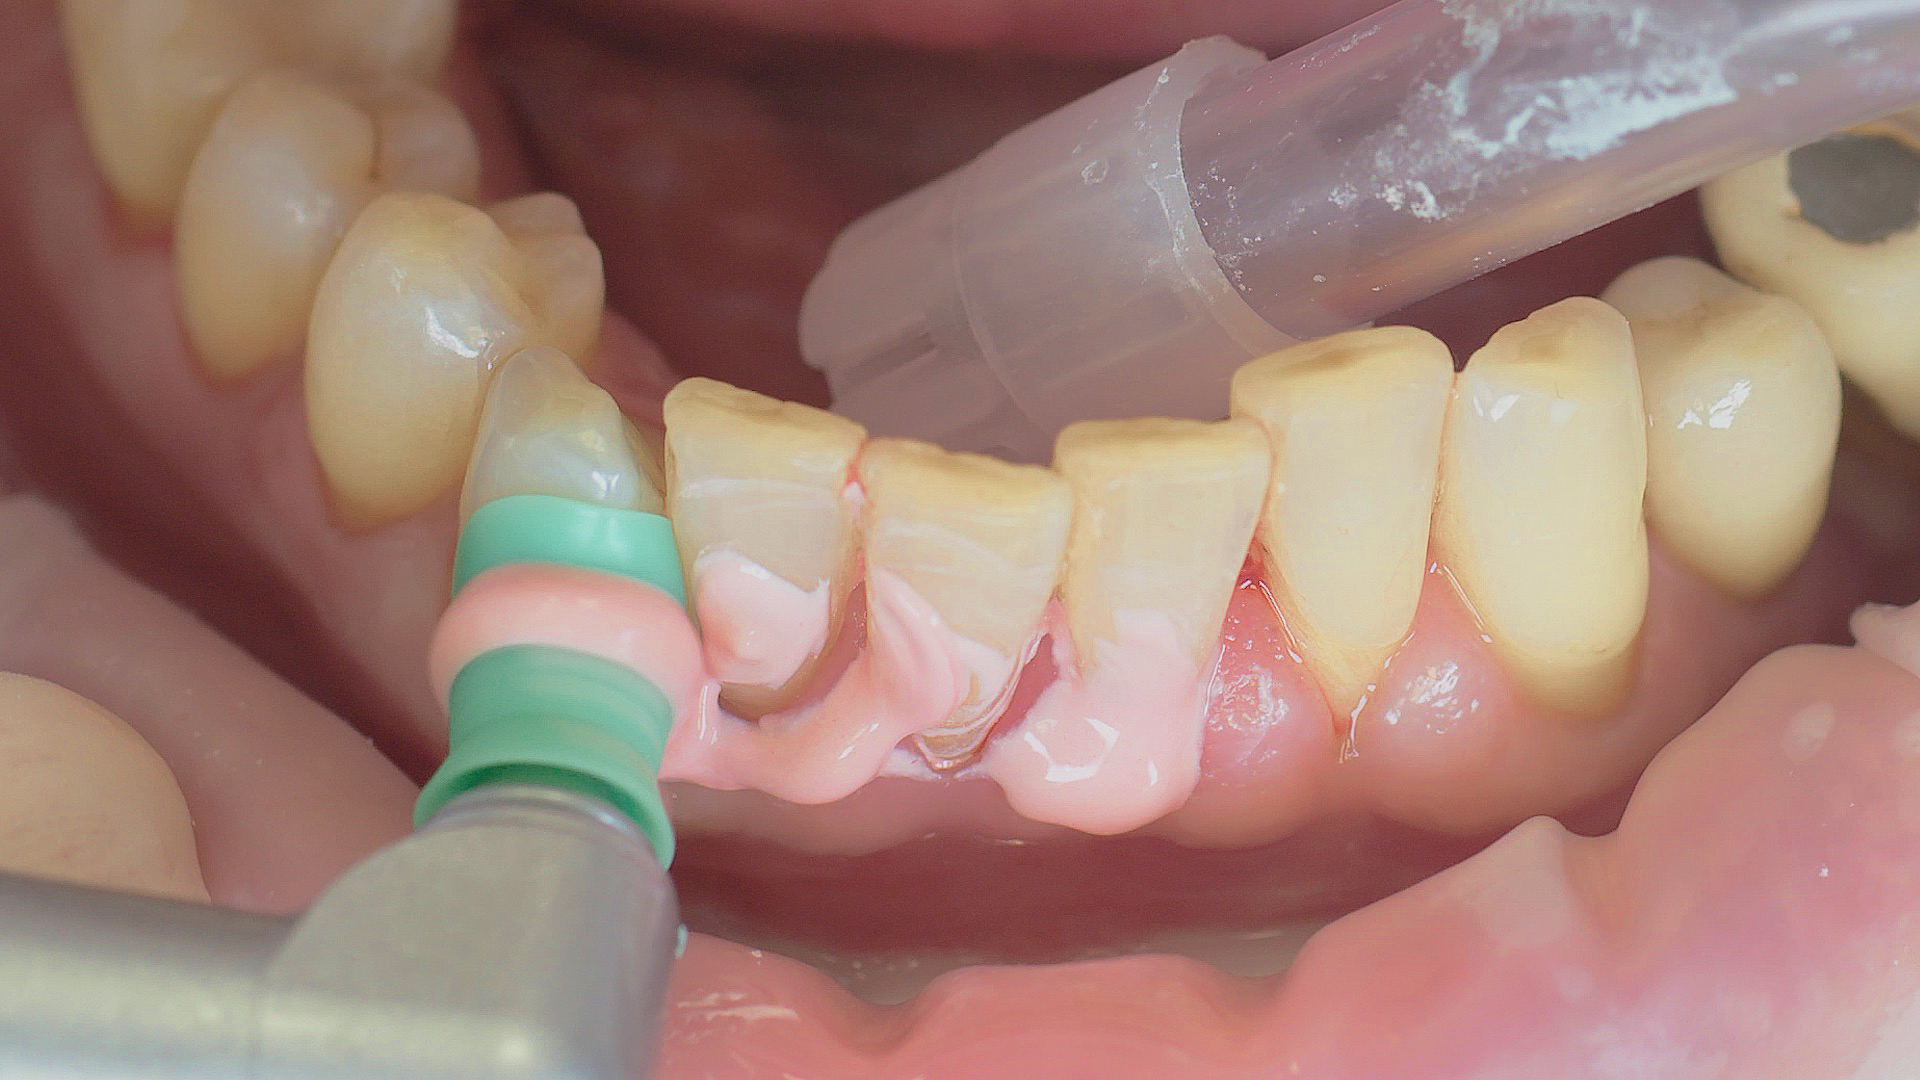

Every dental examination is based on a detailed medical history combined with targeted diagnostics con- taining as much detail as possible: The dentist records systemic risk factors such as diabetes or smoking and identifies any potential increased tendency to inflammation.[3] Hard and soft tissues are examined and periodontal pockets are probed in a screening test according to PSR (Periodontal Screening and Recording). In case of abnormal findings, the periodontal status is then re- corded and therapy is initiated where necessary. This treatment begins with professional biofilm management, by using, for example, rotary cups and polishing com pounds (Fig. 1), and comprehensive instructions in oral hygiene. Sonic or ultrasonic systems remain an effective alternative or supplement to manual instruments for sub- gingival debridement and biofilm management (presentation by Prof. Dr Ulrich Schlagenhauf;

Fig. 2). Supplementary use of photodynamic therapy, air polishing or local and systemic antibiotics is not adequately documented (Prof. Dr Sema Hakki).[4] According to Dr Sergio Bizzarro, improved biomarker diagnostics may lead to an increase in customised patient therapy in the future.